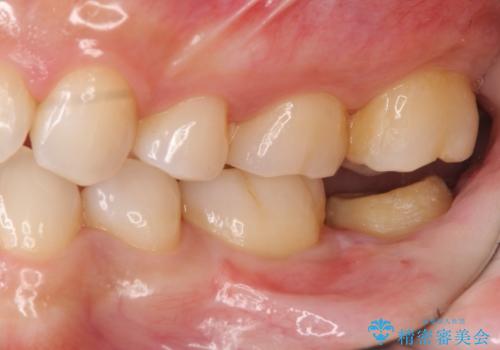

②歯周外科手術を行う。しっかり歯ぐきを下げ、マージンが歯肉縁下深くならないようにする

:虫歯も取り切って、きわがあったものが入るため①のようなことは起こりにくい。しかし外科処置が必要。

他院で難しいと言われた虫歯治療をきっちりすることができて、とても喜んでいただきました。

深刻な状態であればあるほど、長く持つ治療は手間がかかります。(お金もです)